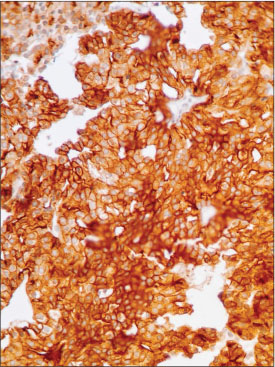

A 50-year-old male presented with two rapidly enlarging tender nodules on the scalp and distal finger of the hand. On physical examination, they were crusted erythematous nodules with focal areas of alopecia on the scalp. Multiple other cutaneous and subcutaneous nodules were evident on the right and left hand and left foot and calf. [Figure 1], [2], [3], [4] show the cutaneous nodules on scalp, both hands, and left foot and calf on further examination of the patient. Core biopsies of the scalp and hand nodules were sent for histopathological examination (HPE). Hematoxylin and eosin (H and E) stained sections showed tumor cells arranged in a lobular, microcystic, and acinar pattern. [Figure 5] and [6] show the low power and high power view (?10 and ?40, respectively), of round to polygonal tumor cells with basophilic granular to clear cytoplasm, and hyperchromatic nucleus and an inconspicuous to single nucleoli. Acini were comprised of cuboidal cells with clear to vacuolated cytoplasm showing PAS-positive cytoplasmic granules and pleomorphic, hyperchromatic nuclei with frequent atypical mitosis. A diagnosis of low-grade metastatic carcinoma was offered. The primary sites under consideration were the salivary gland, kidney, GIT, and the thyroid gland. Immunohistochemistry (IHC) revealed positive staining for AE1/AE3 [Figure 7], CK7, and DOG1 [Figure 8] and were negative for CK20, vimentin [Figure 9], p63, CDX2, CEA, TTF, PAX8, and S100. PAX8-negative immunostaining ruled out thyroid and renal origin of the metastatic tumor. CK7 positivity and CK20 negativity favored salivary gland origin. p63-negative staining ruled out myoepithelial salivary gland tumor. Further, DOG1 membranous and cytoplasmic positivity and P63 negativity favored ACC. The patient was reexamined clinically after the pathological diagnosis, and a preauricular scar was noted on the patient?s face, confirming a prior parotid surgery 20 years back. Thus, with a history of a previous surgery in the parotid region, HPE and IHC, a diagnosis of metastatic ACC was offered.

|?Figure. 7? AE1 positivity